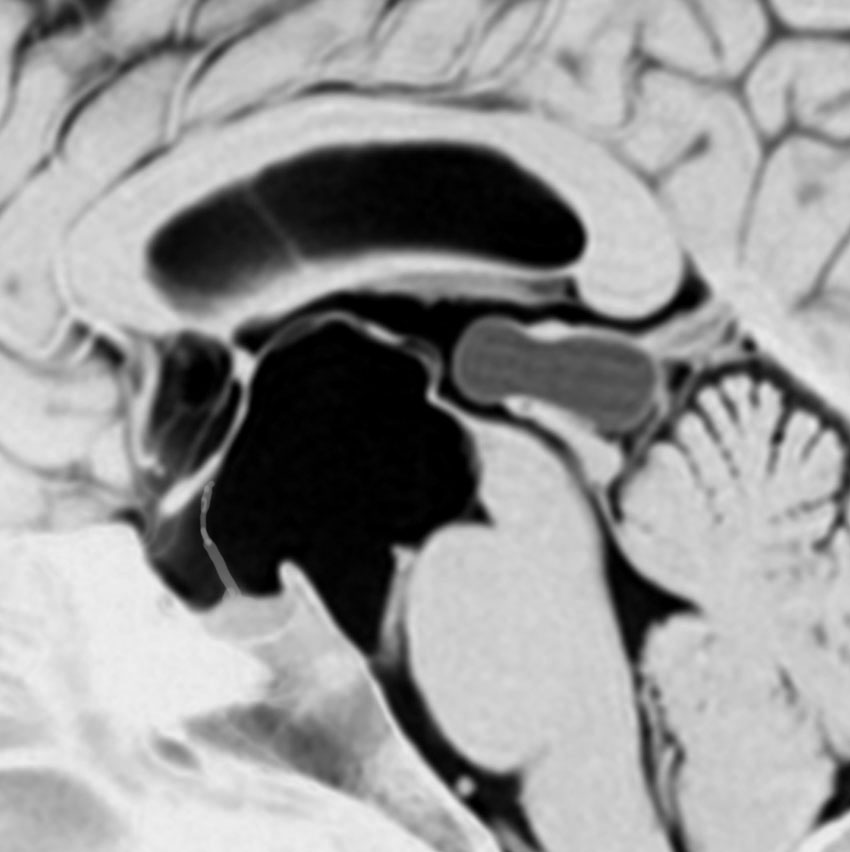

これも成人女性に偶然見つかった松果のう胞です。少し大きめですが,何も治療する必要はありません。中脳水道という所が狭くなっていますが,はっきり閉塞するまでは治療はしません。左がT1強調画像で黒っぽく見えます。右はT2強調画像で白く映っています。